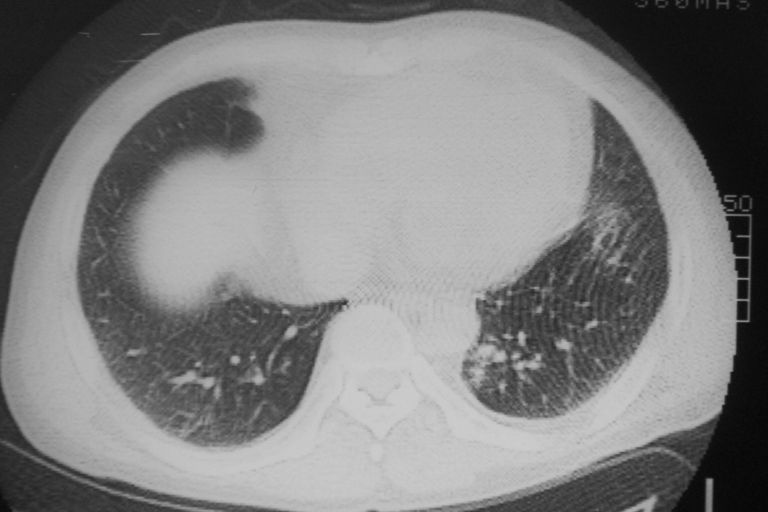

患者 男 50岁 无痛性咯血3天,无其他不适.

1 左肺下叶基底段见两结节软组织密度灶, 肺窗边缘见有毛刺征像, 不能排除占位. 2 建议结合临床治疗一周后ct随访在看其结果.

2心包积液

2、心包积液

2 心包积液。

左下肺结节状软组织密度影,一个边缘有卫星病灶,邻近胸膜增厚.另一个有毛刺.心影周围水样密度影环绕.考虑:

1.肺癌可能.肺tb待排.

2.左侧胸膜增厚.心包积液.